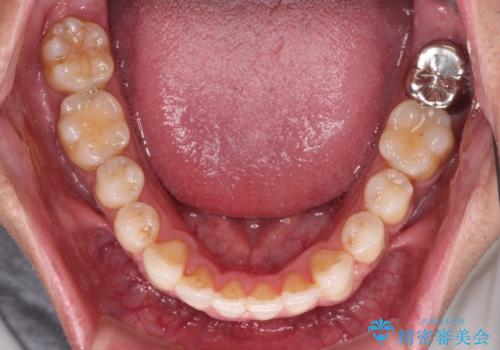

- 上下前歯の叢生を気にして来院された患者様です。

奥歯はクロスバイトとなっているので上顎は側方拡大を行いつつ、上下全体の叢生をインビザラインにより改善することとしました。

治療途中でクリーニングやホワイトニングを行い、歯列が整うと同時に明るい口元となりました。